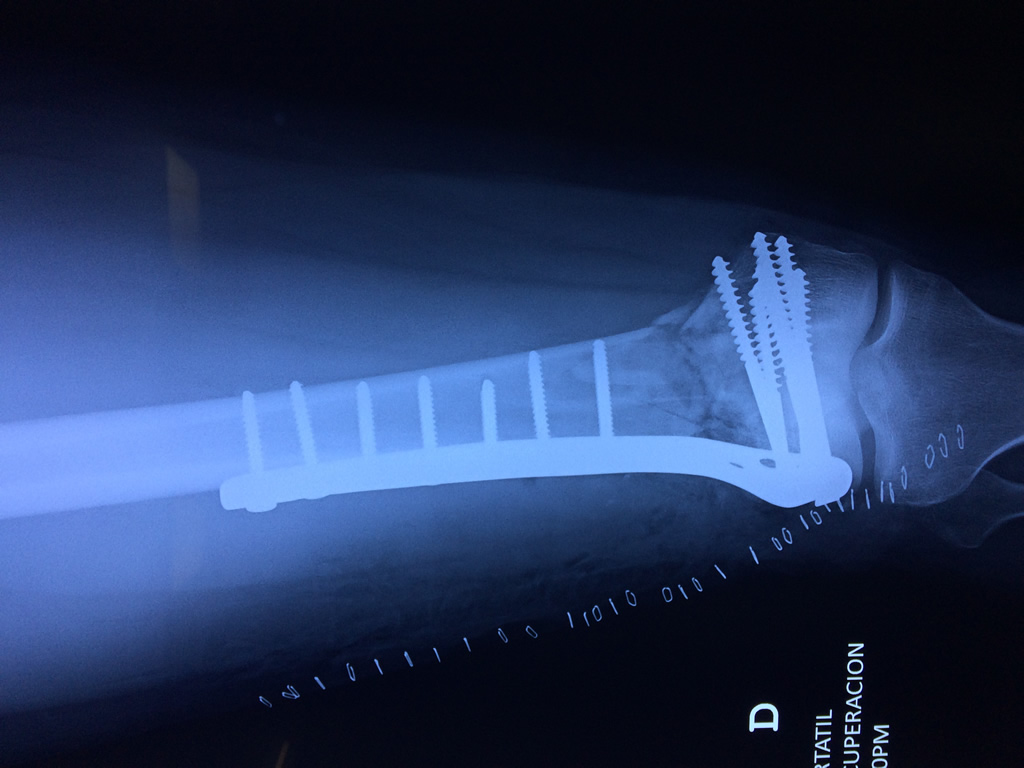

Cirugías de Quiste de Baker